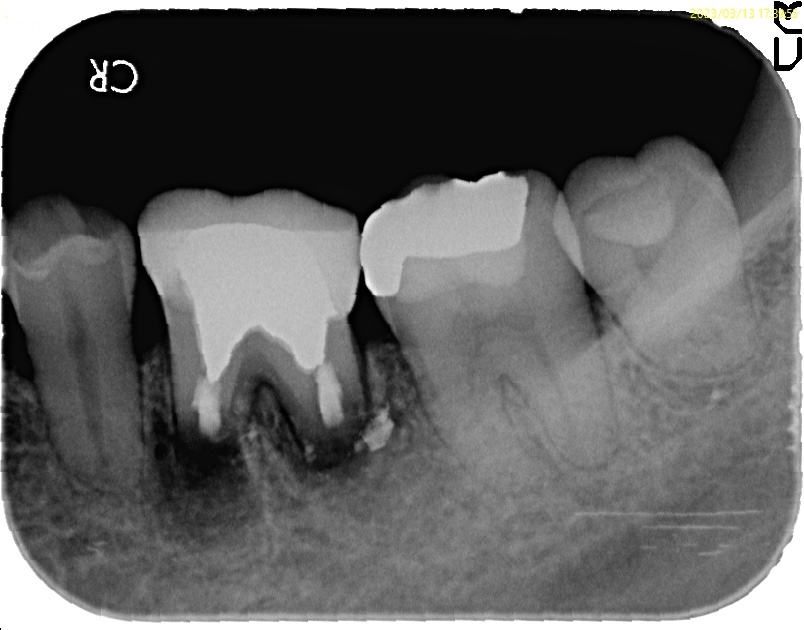

もう諦める?歯根端切除術3年後の経過報告

治療前

治療後

| 診断名 | pulp diagnosis : Previously treated periapical diagnosis : Chronic apical abscess |

| 治療の方法 | 歯根端切除術(左下6番) |

| 治療期間 | 2回 |

| 治療費 | 税込約20万 |

歯肉を剥離した時点で、歯根の先端が出てきました。

歯根の約3mmを切断。2mmでもうまくいくケースもあるでしょうし、4mm必要な時もあるでしょう。

メチレンブルーで染色し、根管を確認

根の先を切るだけでは治りません。

根管内部の感染を取り除く処置(逆根管形成)がとても重要になります。